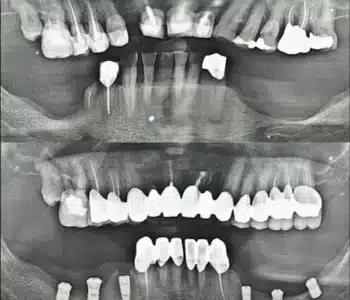

Dr. Seden Aksu is a specialist in modern implantology and surgical dentistry with extensive experience in the management of complex clinical cases. In her practice, she applies comprehensive surgical planning, minimally invasive techniques, and advanced regenerative technologies aimed at restoring both the function of the dentoalveolar system and the aesthetics of the smile. Dr. Aksu has significant experience in performing implant procedures, bone augmentation, and periodontal surgery, including the treatment of patients with severe bone loss. The primary goal of her work is to achieve stable, long-term outcomes in implant rehabilitation and the restoration of oral tissue health.